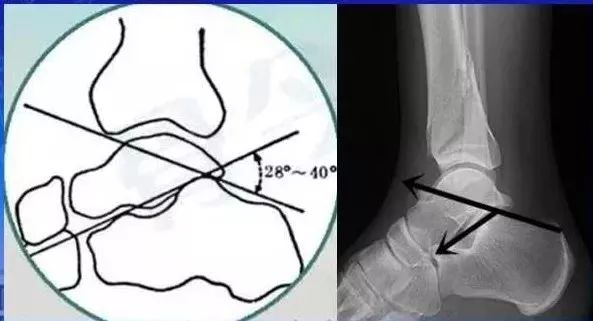

強推 骨關節常用的角度測量方法彙總 一文搞定 雪花新闻

強推 骨關節常用的角度測量方法彙總 一文搞定 雪花新闻

強推 骨關節常用的角度測量方法彙總 一文搞定 雪花新闻

強推 骨關節常用的角度測量方法彙總 一文搞定 雪花新闻